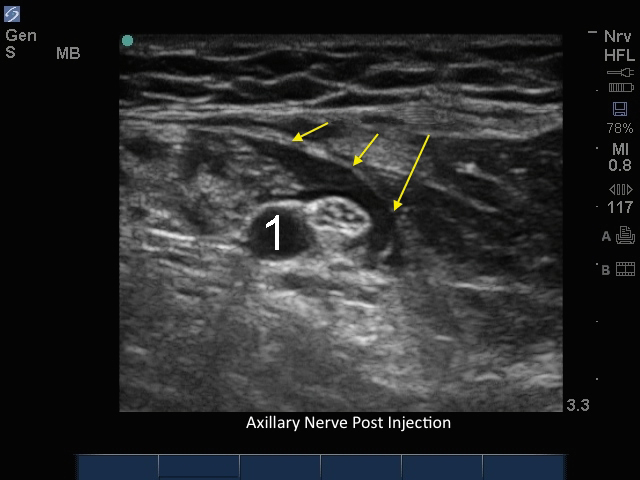

注射后腋神经

箭头:局部麻醉

动脉